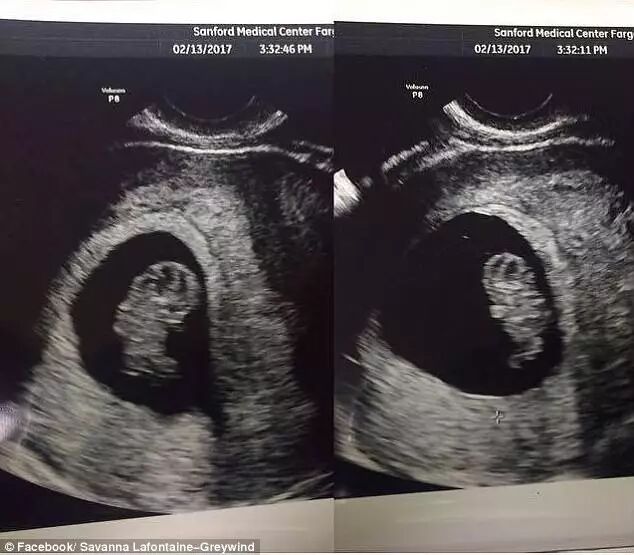

上周日,一具被塑料和胶带包裹的腐烂女尸,被发现漂浮在美国北达科他州Fargo附近的Red River……

经调查,这名女尸就是22岁的女子Savanna Greywind。

而她的死因,

疑似是遭人剖腹取婴而亡..

8月19日前后,怀孕八个月的Greywind突然人间蒸发,失踪了!全家人心急如焚时突然想到,Greywind消失前曾和家人说过,她要去帮邻居Brooke Lynn Crews缝裙子。

发现了出生2天的女婴,

而她正是Greywind死前腹中的婴儿!